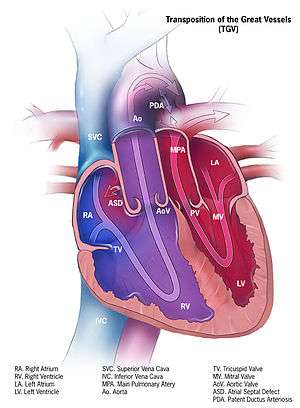

| Illustration of transposition of the great vessels | |

Transposition of the great vessels (TGV) is a group of congenital heart defects involving an abnormal spatial arrangement of any of the great vessels: superior and/or inferior venae cavae, pulmonary artery, pulmonary veins, and aorta. Congenital heart diseases involving only the primary arteries (pulmonary artery and aorta) belong to a sub-group called transposition of the great arteries.

Dextro-Transposition of the great arteries

In dextro-Transposition of the great arteries (dextro-TGA) deoxygenated blood from the right heart is pumped immediately through the aorta and circulated to the body and the heart itself, bypassing the lungs altogether, while the left heart pumps oxygenated blood continuously back into the lungs through the pulmonary artery. In effect, two separate "circular" (parallel) circulatory systems are created. It is called a cyanotic congenital heart defect (CHD) because the newborn infant turns blue from lack of oxygen.

In many cases, TGV is accompanied by other heart defects, the most common type being intracardiac shunts such as atrial septal defect including patent foramen ovale, ventricular septal defect, and patent ductus arteriosus. Stenosis, or other defects, of valves and/or vessels may also be present.